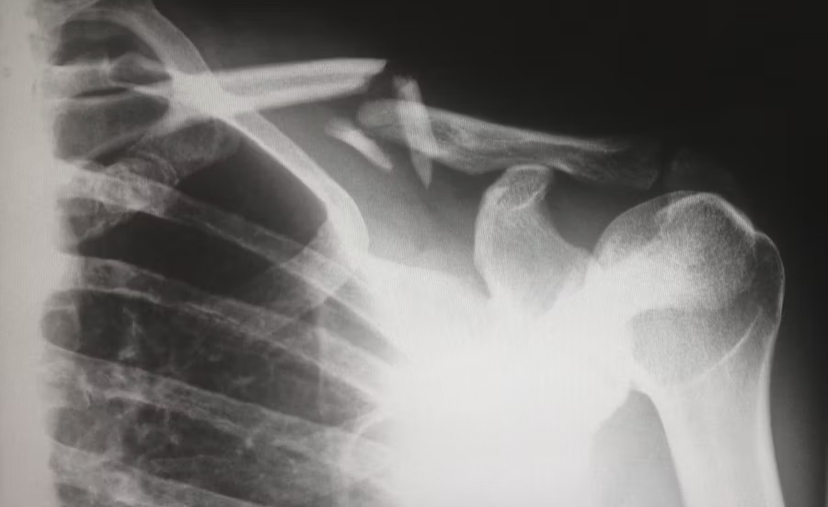

외상을 입은 후 위와 같은 증상이 있다면, 꼭 병원을 방문해 엑스레이나 CT 검사를 통해 정확한 진단을 받으시길 바랍니다.